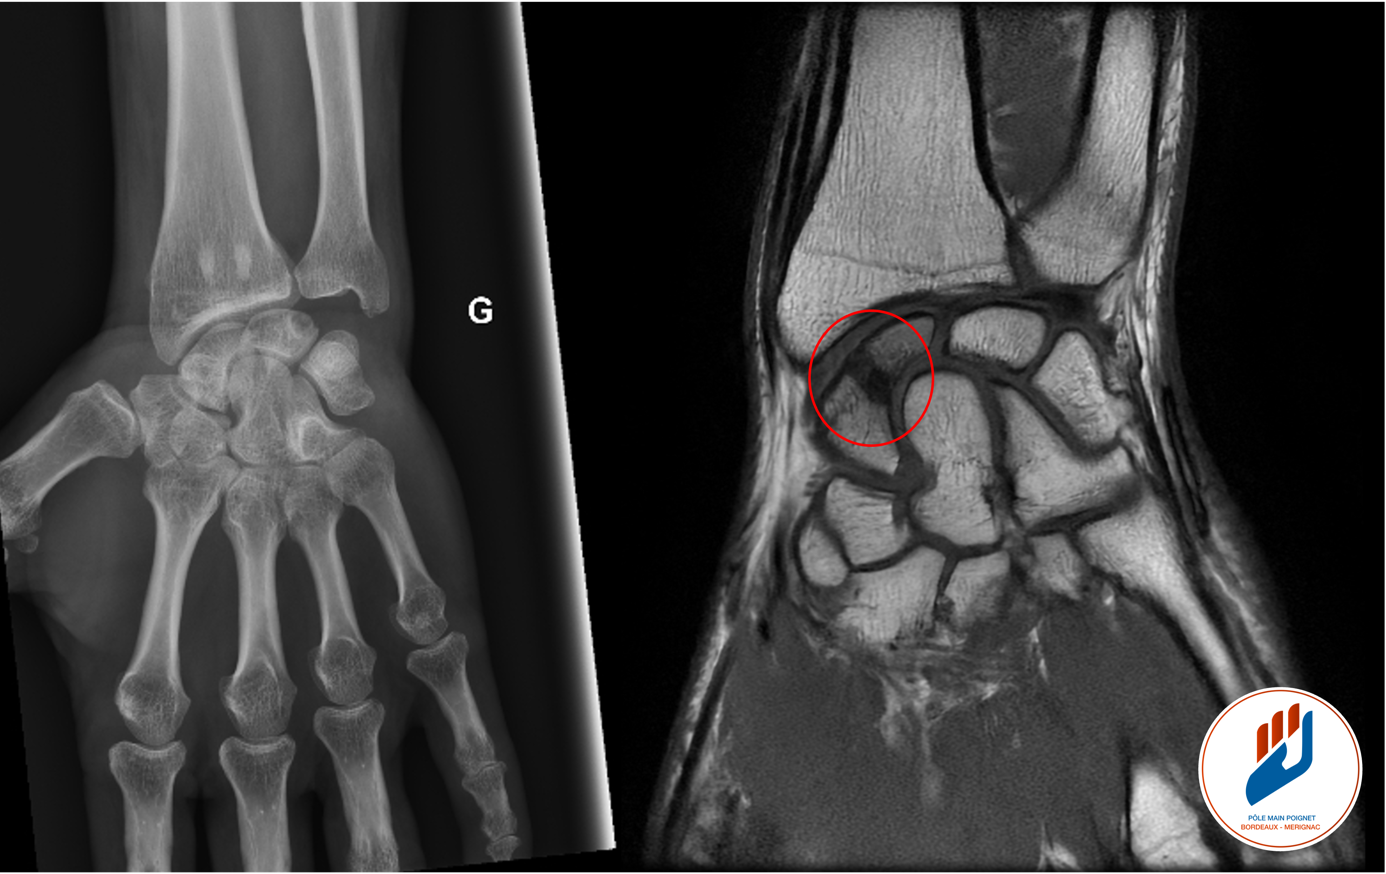

La radiographie est l’examen de première intention. Toutefois, dans de nombreux cas, la fracture du scaphoïde est invisible à la radiographie initiale. C’est pourquoi une consultation dans un centre spécialisé est nécessaire : Lorsque la douleur persiste malgré une radio normale, un scanner ou une IRM est souvent nécessaire. Ces examens permettent de confirmer le diagnostic et de préciser le type de fracture.

Figure 1: Suite à une chute sur le poignet, une douleur persiste au niveau du poignet gauche malgré une radiographie normale. Une fracture du scaphoïde est confirmée par IRM au niveau du poignet droit.